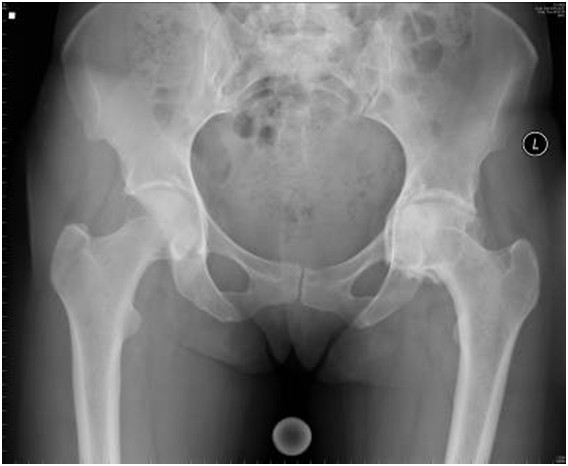

Poniższy radiogram stawów biodrowych w projekcji AP przedstawia:

Pytanie 40